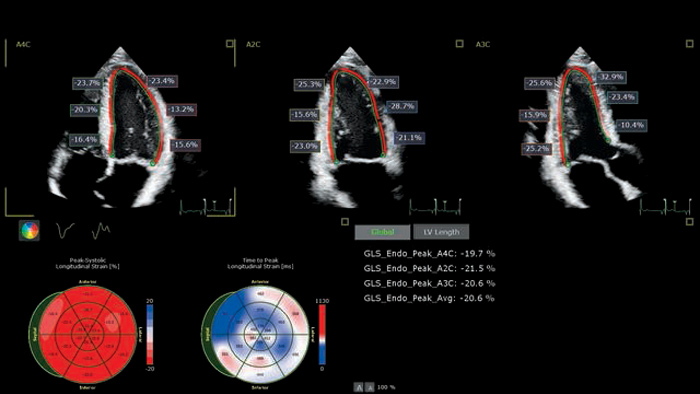

Streamline echocardiography workflow across your organization with Philips Ultrasound Workspace. Built on the legacy of the TOMTEC ARENA platform, it allows for greater efficiency in viewing, analysis and reporting by giving care teams the flexibility to adopt different workflows based on their current and future needs.

The EPIQ CVx is a dedicated cardiac ultrasound solution which brings significant advancements in functionality. This helps you deliver better care through higher processing power, exceptional imaging with more clarity & sharpness, improved exam efficiencies, complemented by the proven, robust quantification capabilities of Ultrasound Workspace.